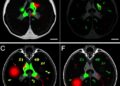

Disease progression is characterized by nerve cell decay that thins the walls of the retina, the layer of tissue that lines the back of the eyeball. The disease also affects the microscopic blood vessels, or microvasculature, of the retina. These characteristics present an opportunity to leverage the power of AI to examine images of the eyes for signs of Parkinson’s disease.

The results indicated that the machine learning networks can classify Parkinson’s disease based on retina vasculature, with the key features being smaller blood vessels. The proposed methods further support the idea that changes in brain physiology can be observed in the eye.